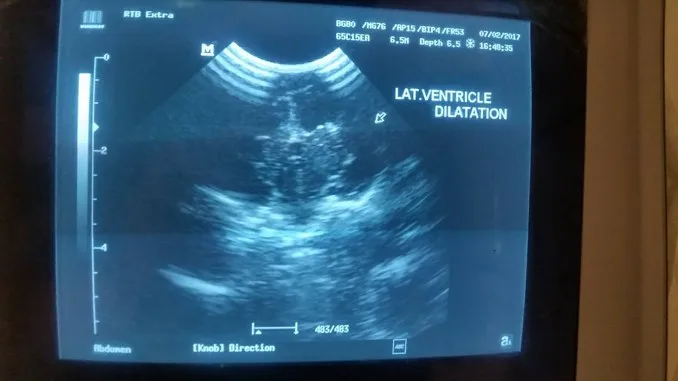

คุณหมอจึงตั้งข้อสงสัยว่าน้องอาจจะมีภาวะน้ำในสมองมากเกินไปจนไปกดเบียดเนื้อสมองหรือที่เรียกว่า โรคหัวบาตร (Hydrocephalus) แต่กำเนิด จึงได้ทำการตรวจเพิ่มเติมด้วยการ Ultrasound จึงพบลักษณะการขยายขนาดขึ้นอย่างผิดปกติของช่องว่างในสมอง ดังภาพ

ซึ่งเป็นลักษณะที่สอดคล้องกับโรคหัวบาตร